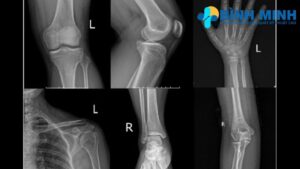

Phòng khám sử dụng máy X quang kỹ thuật số tiên tiến, đạt chuẩn quốc tế, cung cấp hình ảnh sắc nét và chi tiết. Công nghệ này giúp giảm thiểu lượng tia X, đảm bảo an toàn cho bệnh nhân, đồng thời hỗ trợ bác sĩ phát hiện chính xác các tổn thương xương khớp.

Chụp X quang xương khớp là phương pháp chẩn đoán hình ảnh quan trọng, giúp bác sĩ phát hiện sớm các vấn đề về xương và khớp, bao gồm:

- Gãy xương: Xác định vị trí và mức độ gãy xương do chấn thương.

- Thoái hóa khớp: Phát hiện dấu hiệu mòn sụn, gai xương hoặc hẹp khe khớp, thường gặp ở khớp gối, cột sống, hoặc khớp háng.

- Viêm khớp: Nhận diện các dấu hiệu viêm khớp dạng thấp, viêm cột sống dính khớp, hoặc viêm khớp do gout.

- Loãng xương: Đánh giá mật độ xương để phát hiện nguy cơ loãng xương hoặc xương dễ gãy.

- Dị dạng xương khớp: Phát hiện các bất thường bẩm sinh hoặc do bệnh lý như lệch cột sống, trật khớp.